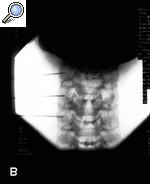

Con el paciente en decúbito supino y el cuello en ligera hiperextensión, se realizan 4 movimientos con el arco de rayos (Rx). Con el Rx en posición lateral, se identifica el nivel que se va a tratar. Cuando se ha identificado, se realiza un movimiento del Rx en posición oblicua hasta que se visualiza el foramen completamente). Cuando el foramen se ve claramente, se realiza un movimiento craneocaudal para eliminar el doble contorno del agujero que se va a tratar. Por último, con una proyección anteroposterior, se debe visualizar la punta de la aguja en la porción media de la articulación facetaria.

Figura 1. A: proyección oblicua de la columna cervical en la que se puede ver que la aguja se dirige a la parte posterior del foramen. B: proyección anteroposterior donde se aprecia que la aguja sobrepasa la línea facetaria.

Anatómicamente, se debe tener en cuenta que la arteria vertebral ocupa la parte anterior del agujero de conjunción, por lo que es de suma importancia, para evitar complicaciones nefastas4,5, el acercamiento en la parte posterior; asimismo es importante saber que el primer agujero que se visualiza es el que corresponde a C3 y, por último, que en la zona cervical la raíz sale por encima del cuerpo vertebral correspondiente (la raíz C4 sale entre C3 y C4). El punto diana es la porción inferior del agujero radicular, ya que el ganglio dorsal de la raíz se localiza en la unión de los tercios medio e inferior del foramen.